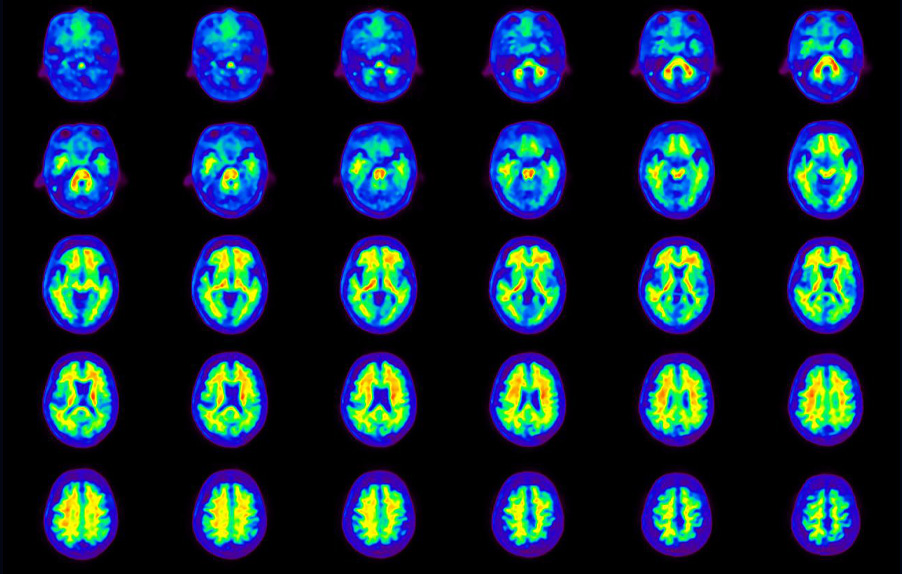

Head / Case4 : Amyloid

Axial

Courtesy : Kindai University Hospital

- Imaging protocol

- Injected dose: 3.21 MBq/kg, 18F-Flutemetamol

- Uptake time: 100 minutes

- Scan time: 20 minutes